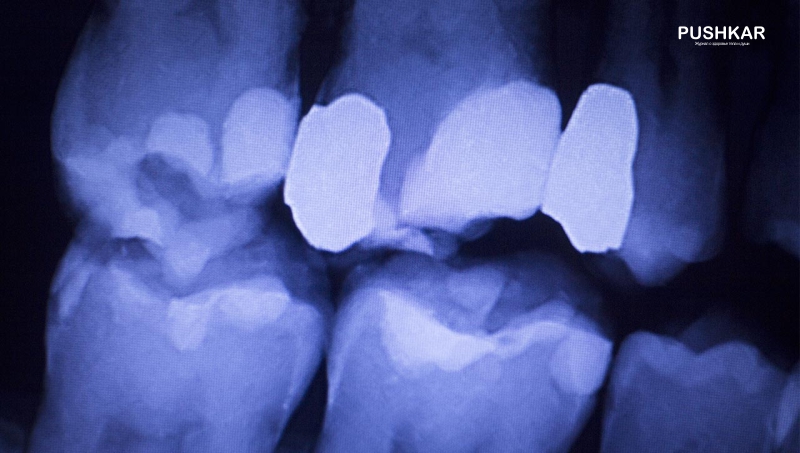

Кариес, пародонтит и периодонтит - это инфекционные заболевания. Антимикробные пептиды (AMP) являются естественными антибиотиками, которые являются частью иммунной системы. AMP убивают ротовые бактерии, которые вызывают кариес и периодонтит, при условии, что уровень витамина D в крови достаточно высок. Добавление солнечного света или витамина D обеспечивает достаточное содержание витамина D в организме. Исследование, проведенное в Голландии, показало у 59% исследованных людей дефицит витамина D зимой - содержание витамина D в крови меньше 50 нмоль/л. Содержание витамина D, по меньшей мере, 50 нмоль/л может быть достаточным для абсорбции кальция и метаболизма кальция, необходимого для сильных костей и зубов. Однако для иммунной системы, необходимой для профилактики различных заболеваний, требуется содержание витамина D примерно 80-100 нмоль/л.